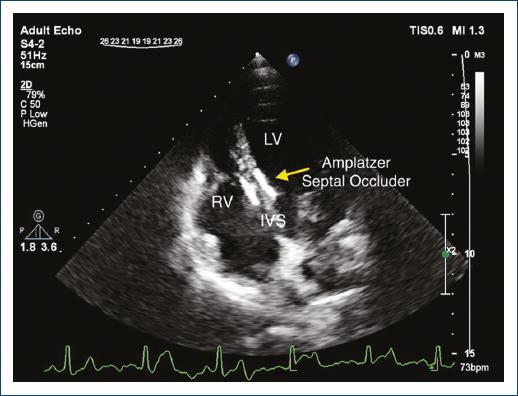

A 25-year-old woman presented to our echocardiography laboratory for a follow-up imaging study. She had a history of muscular ventricular septal defect (VSD) closure by Amplatzer Muscular VSD Occluder (St. Jude Medical, USA) 4 years before this visit. Since this repair, she has remained asymptomatic and was on no medication. In transthoracic echocardiography, the double disc device was visualized in apical four-chamber view (Fig. 1) with no residual VSD flow. Interestingly, in off-axis view of parasternal long-axis imaging, the device was visualized in the form of two side-by-side figure of 8 “Clover-leaf” appearances (Figs. 2 and 3).

Figure 1/Video 1 Apical four-chamber echocardiogram showing normal biventricular function. The double-disc occluder device is visualized in the mid part of the interventricular septum.